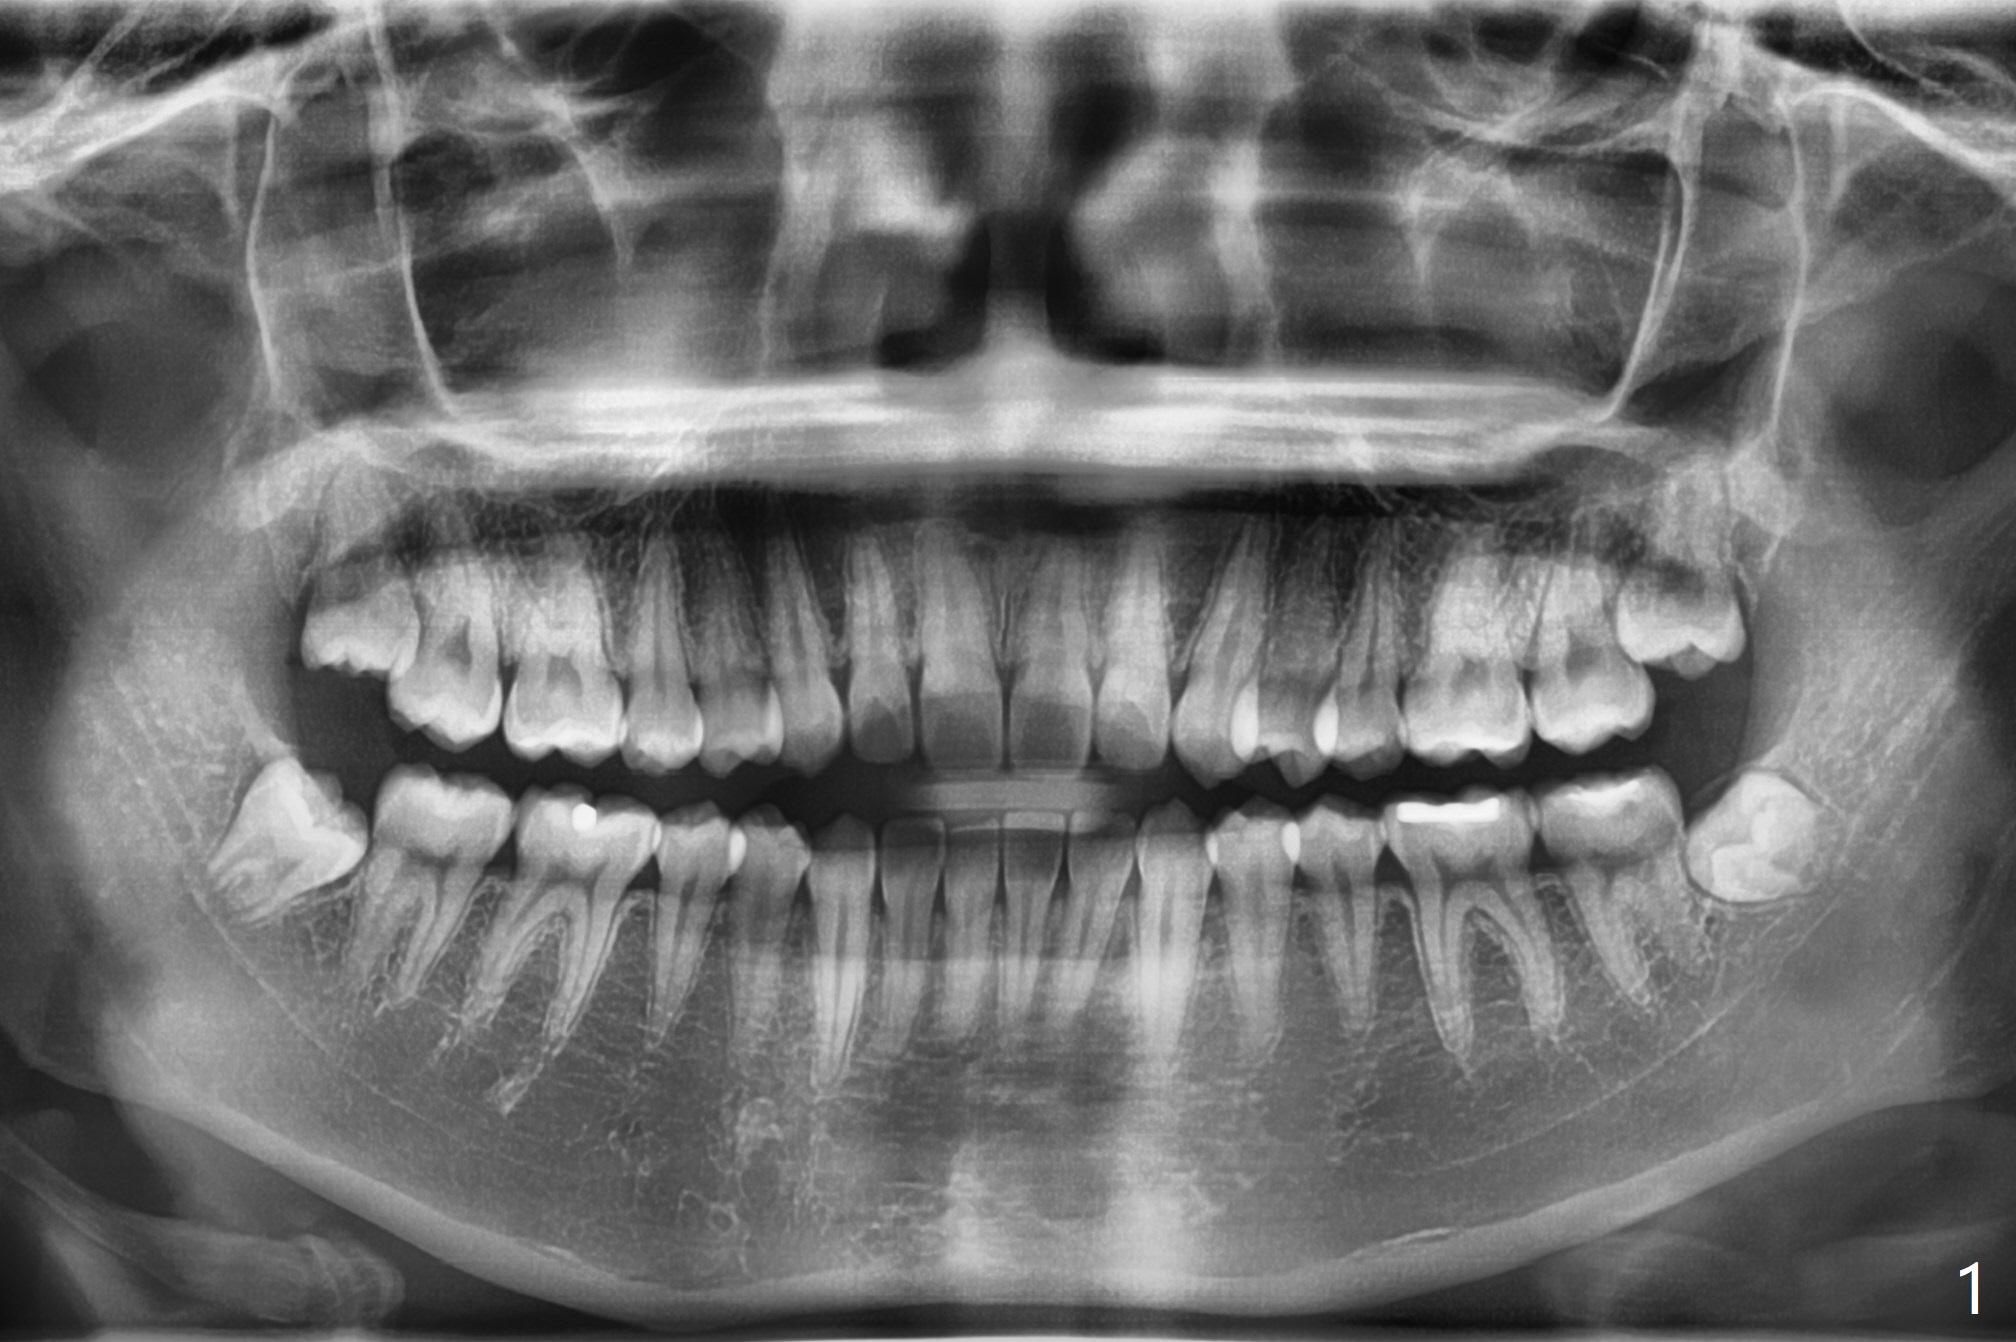

A 18-year-old woman with suboptimal oral hygiene had pericoronitis at #1 and 17 (Fig.1). To prevent dry socket, collagen plug is placed at #17 and 32 post extraction (Fig.2). She is uninterested in bone graft, which turns out unnecessary for young patients.